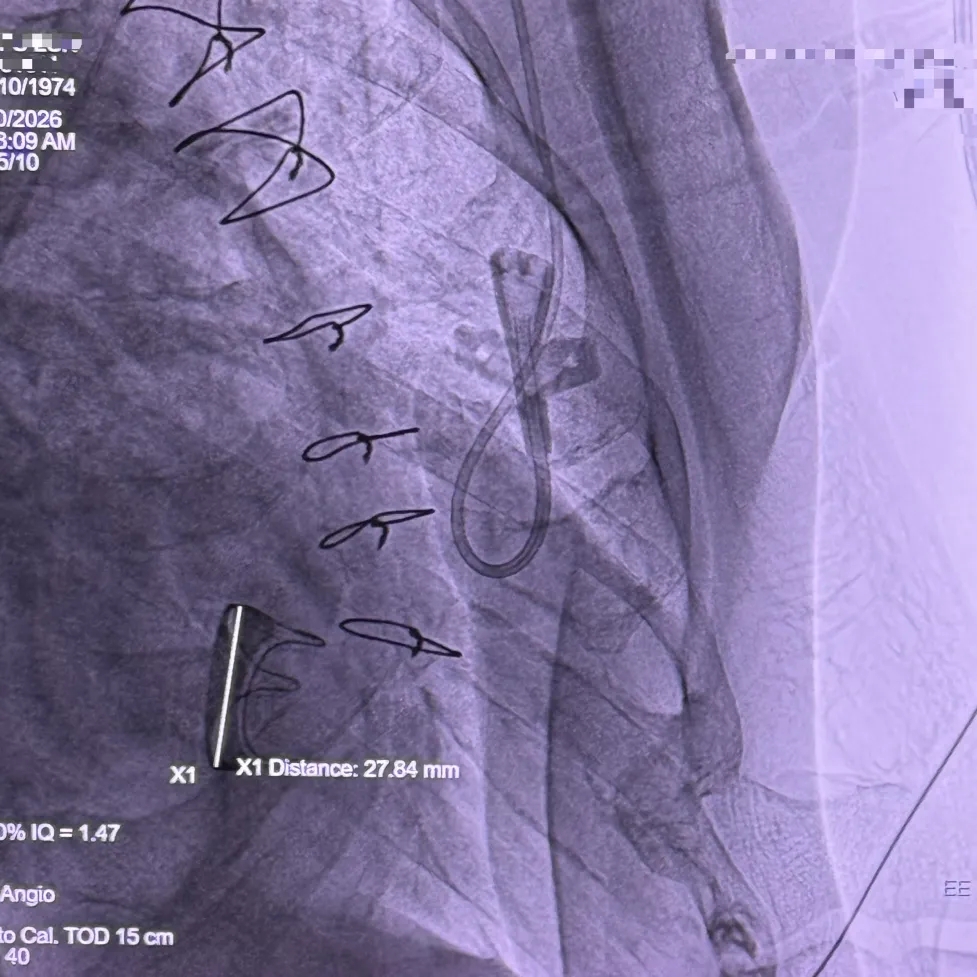

术中影像

右侧垫肩,基本打平原外科瓣瓣架,工作体位:RAO29° CRA12°

直头导丝顺利跨瓣

Mark点平齐外科瓣瓣架低端进行定位

瓣膜全展开位可见同轴稍差,心房内上浅下深

瓣膜回收后,旋转输送器弯型调整同轴

瓣膜重新释放至全展开位,可见位置合适,流出端可见形态压缩

超声评估瓣膜位置可,无瓣周漏

瓣膜稳定脱钩

28mm球囊后扩,瓣膜形态明显改善

最终评估可见瓣膜形态、位置均理想